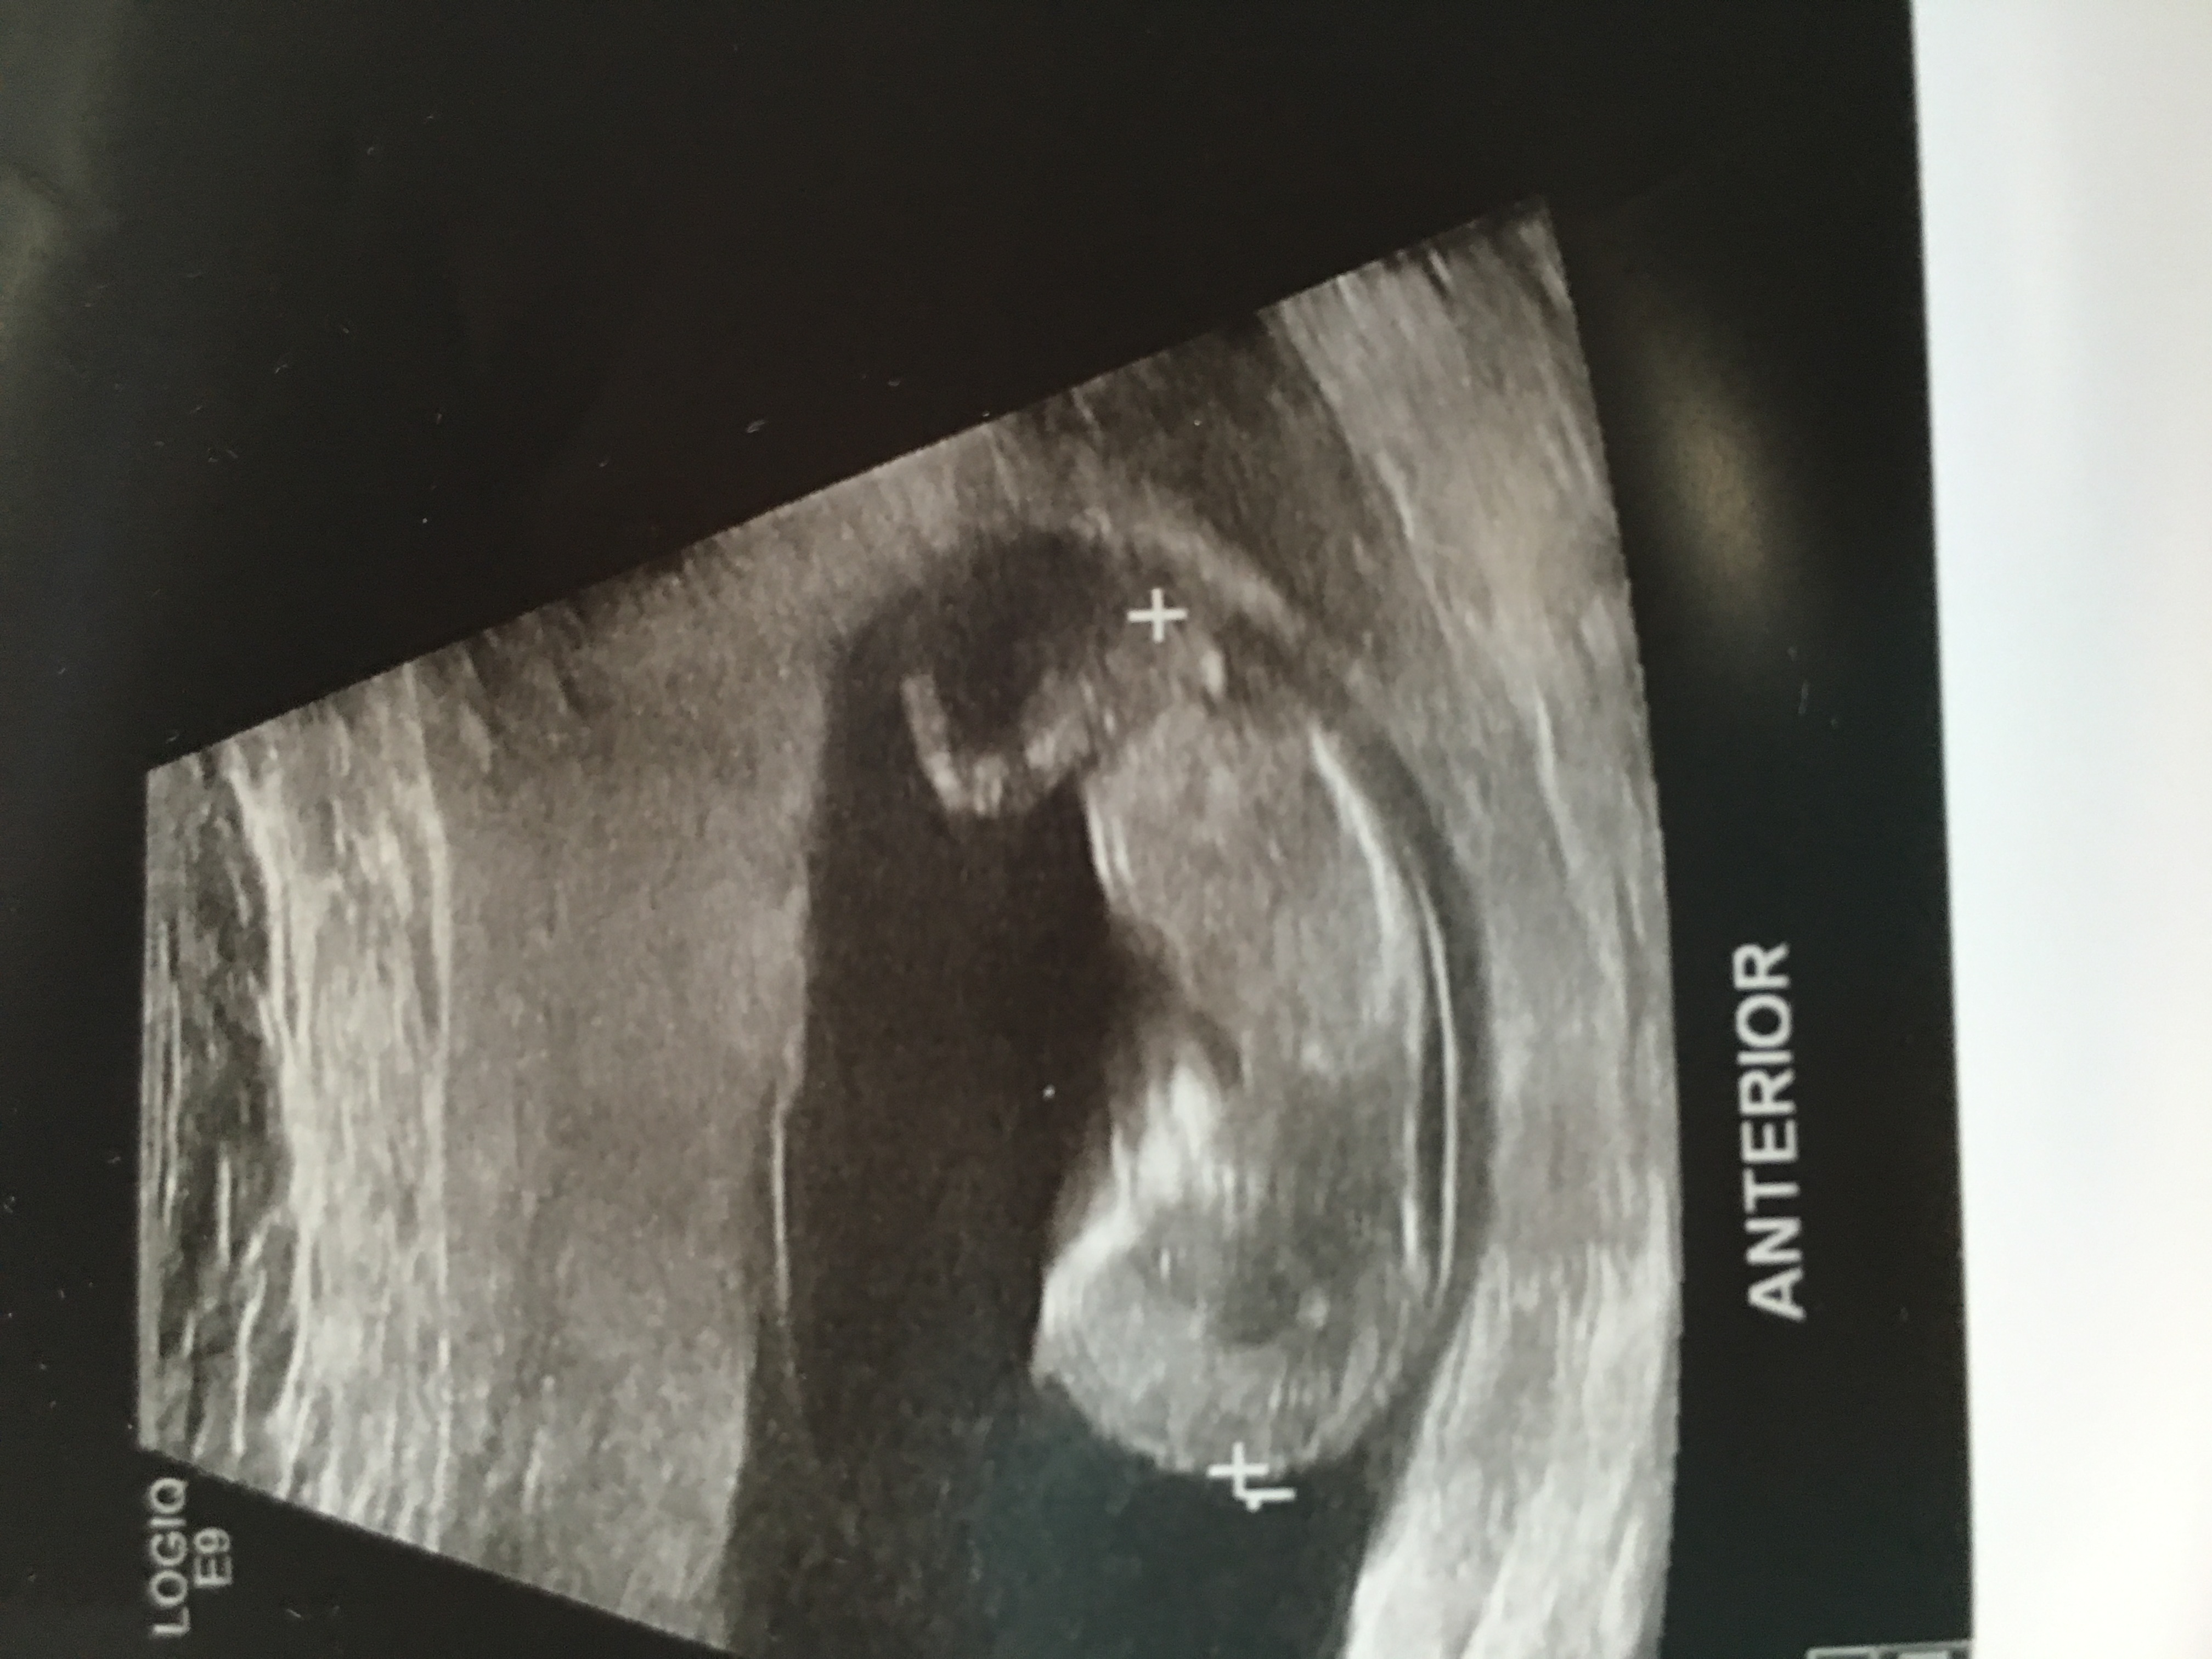

Any Guesses 11w6d